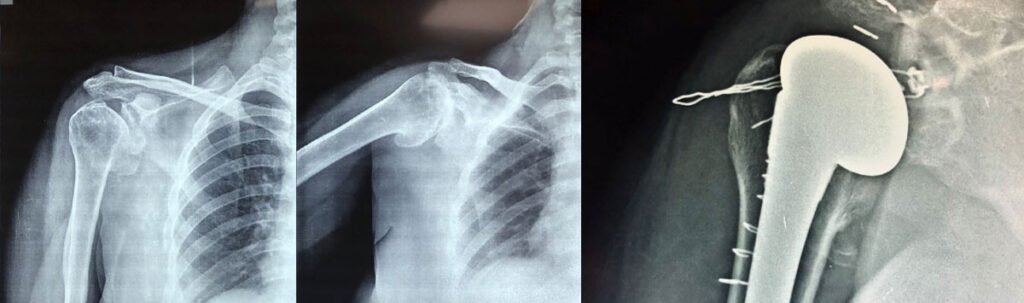

Another type of shoulder replacement is called reverse total shoulder replacement. Reverse total shoulder replacement is used for people who have:

Completely torn rotator cuffs that is the muscles with in shoulder complex and Severely osteoarthritis of shoulder (cuff tear arthropathy) or a case of a previous shoulder replacement that failed.

For these individuals, a conventional total shoulder replacement can still leave them with pain. They may also be unable to lift their arm up past a 90-degree angle. Not being able to lift one’s arm away from the side can be severely debilitating. In reverse total shoulder replacement, the socket and metal ball are switched. That means a metal ball is attached to the shoulder bone and a plastic socket is attached to the upper arm bone. This allows the patient to use the deltoid muscle instead of the torn rotator cuff to lift the arm.